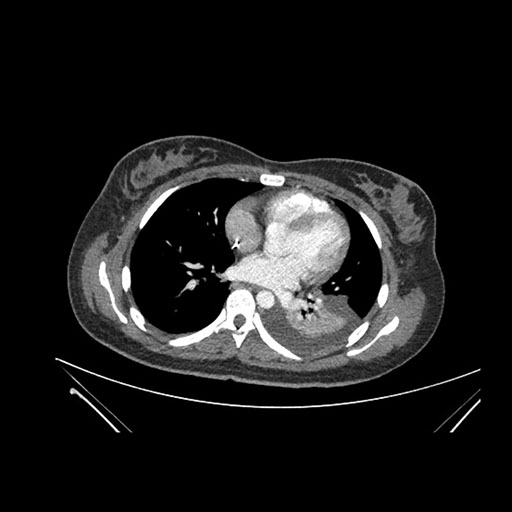

Look through the patient's CT scan to identify any areas of concern for the necessary procedure.

Imaging analysis

Based on initial findings, which issue(s) would you be most concerned about?

Considering the patient’s issues, what would be your next step?